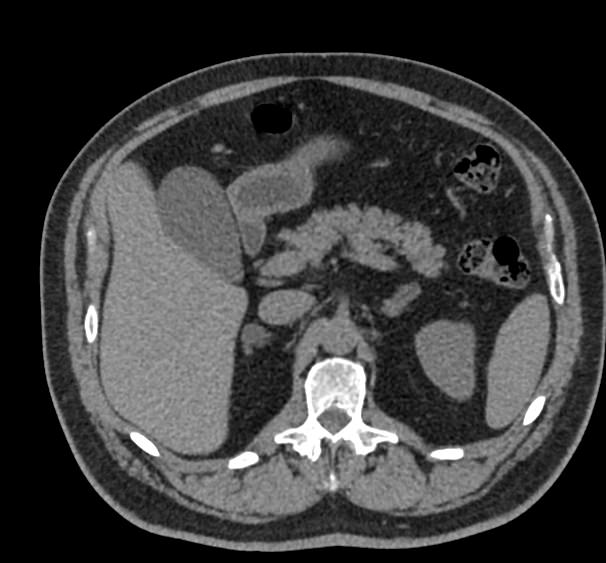

Современным высокоинформативным способом выявления патологических изменений поджелудочной железы является мультиспиральная компьютерная томография с прицельным сканированием органа.

При помощи специальных цифровых приложений данные, полученные при сканировании, преобразуются в трехмерные изображения органа, что дополнительно повышает точность и достоверность диагностики заболеваний поджелудочной железы.

Контрастирование позволяет отличить зоны воспаления, деструкции, разрастания фиброзной ткани и опухолевой трансформации от сохраненной паренхимы поджелудочной железы. КТ поджелудочной железы с контрастированием дает исчерпывающую информацию о состоянии органа и патологических процессах в нем.

Что покажет КТ поджелудочной железы

- злокачественные и доброкачественные опухоли, включая инсулиному, глюкагоному, випому, гастриному, рак поджелудочной железы;

- кальцинаты в панкреатических протоках;

- острую и хроническую формы панкреатита;

- кисты и псевдокисты поджелудочной железы